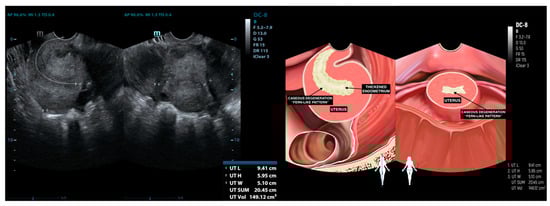

| 10 | AS (44) * | Ill−defined mass at the anterior | Adhesion complex with hydrosalpinx right fallopian tube | Hydrosalpinx | Enlarged with multilocular cystic filled with complex fluid | Not visualized | (−) | (−) |